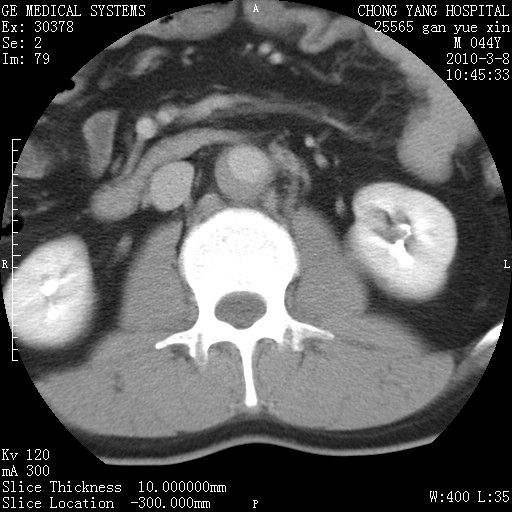

标题: CT24940:主动脉增强,典型病例。 [打印本页]

标题: CT24940:主动脉增强,典型病例。

夹层动脉瘤。

动脉夹层

夹层动脉瘤,典型

主动脉夹层。

动脉夹层的分型:

⒈debakey分型:根据主动脉夹层累及部位,分为三型:ⅰ型:原发破口位于升主动脉或主动脉弓部,夹层累及升主动脉、主动脉弓部、胸主动脉、腹主动脉大部或全部,少数可累及髂动脉。ⅱ型:原发破口位于升主动脉,夹层累及升主动脉,少数可累及部分主动脉弓。ⅲ型:原发破口位于左锁骨下动脉开口远端,根据夹层累及范围又分为ⅲa,ⅲb。ⅲa型:夹层累及胸主动脉。ⅲb型:夹层累及升主动脉、腹主动脉大部或全部。少数可累及髂动脉。

⒉stanford分型:a型:夹层累及升主动脉,无论远端范围如何。b型:夹层累及左锁骨下动脉开口以远的降主动脉。

夹层动脉瘤,少量胸水

夹层动脉瘤;左侧少量胸腔积液。

典型主动脉夹层。